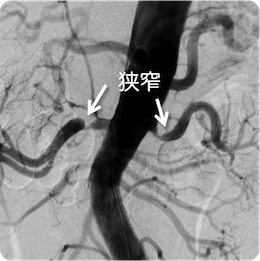

両側腎動脈狭窄

高血圧、腎機能の悪化、心肥大にて発見された両側腎動脈狭窄症。 両側ともステントを留置し、血圧、腎障害の改善を認めました。